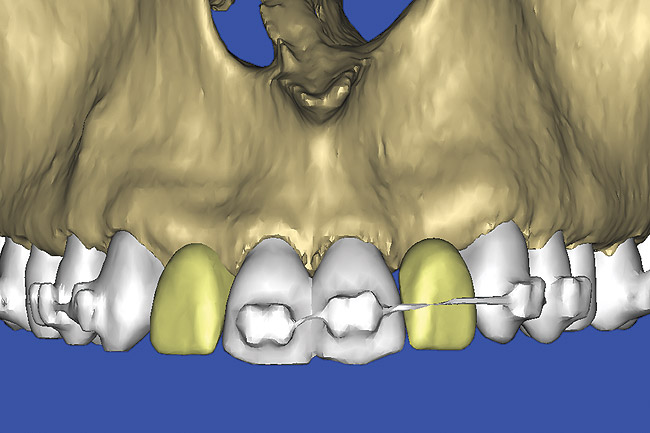

Figure 13  SOFTWARE IMAGING This allowed for evaluation of virtual implant placement to ensure the facial cortical plate was not perforated.

Figure 13

Figure 14  SOFTWARE IMAGING By using the masking feature, the inner and outer layers of bone were removed virtually, revealing the enamel and root structure of the teeth and the rotated position of the right central.

Figure 14